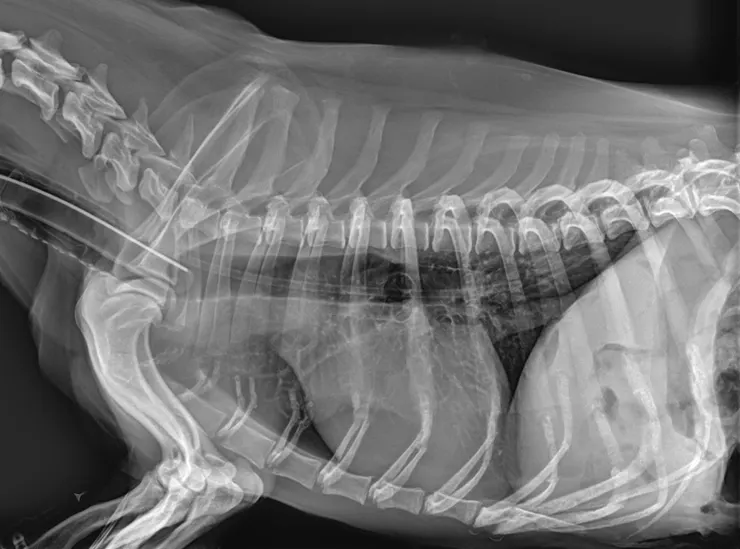

圖為明明已經插著ET tube,還是可以進去氣管的調皮NG tube

管子越放越多,難免就會遇到鬼。用喉頭鏡看老半天還插不太進去的聲門,遇到鼻胃管好像就會自動敞開。會咳嗽的都還好說,偏偏有人氣管裡多了根管子卻還是不咳,如果沒有發現直接餵食,後果實在不堪設想。目前大部分都還是以X光作為最主要的判斷依據,但如果X光室距離很遠,或是傳染病或重症動物不適合移動的情況,有沒有其他替代的方式呢?這篇文獻討論了四種可能的檢測方式,並蒐集了51隻裝鼻胃管的狗,以X光作為gold standard來評斷這四種方式判斷鼻胃管位置是否正確的準確度。其中45隻位置正確,6隻放到氣管(11%的機會真的不能說低啊)。